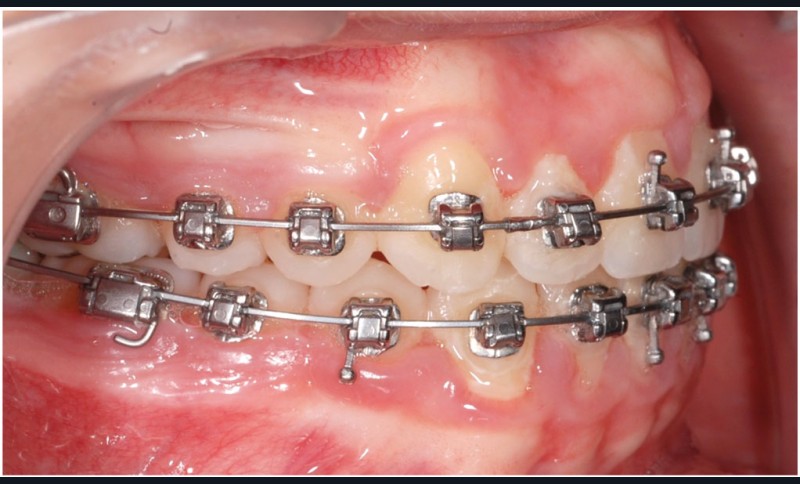

Le cas d’Anthony âgé de 11 ans et 7 mois qui présente une endomaxillie bilatérale associée à un léger encombrement mandibulaire dans un contexte de classe I squelettique hyperdivergente (fig. 1 à 10) est très représentatif de ce que peuvent apporter les forces légères appliquées aux alvéoles dentaires tout en intégrant des torques spécifiques qui permettent de contrôler parfaitement l’orientation radiculaire (fig. 11 à 29).

Le système laisse beaucoup de liberté dans l’interface entre bracket et arc : la vascularisation, et donc le recrutement cellulaire et la reconstruction osseuse s’en trouvent améliorés, la mise en place de l’occlusion se fait sous le contrôle de la matrice fonctionnelle, car les forces engagées restent en dessous de la puissance des forces masticatrices notamment.

Sans aucun appareillage d’expansion, le maxillaire a été transformé et semble avoir été soumis à une disjonction (fig. 30).